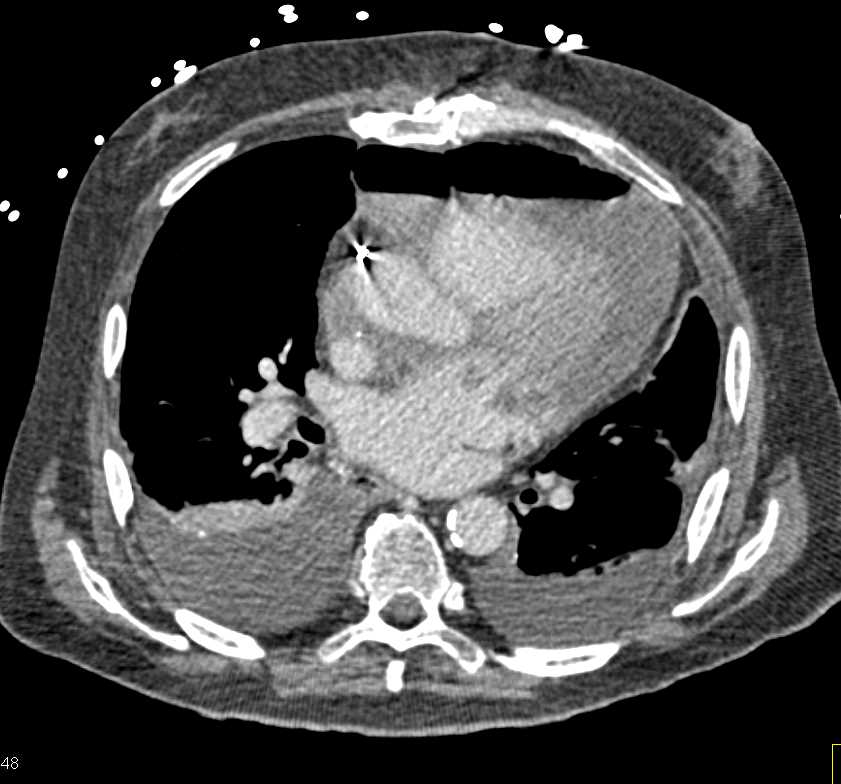

Post Cardiac Surgery Changes